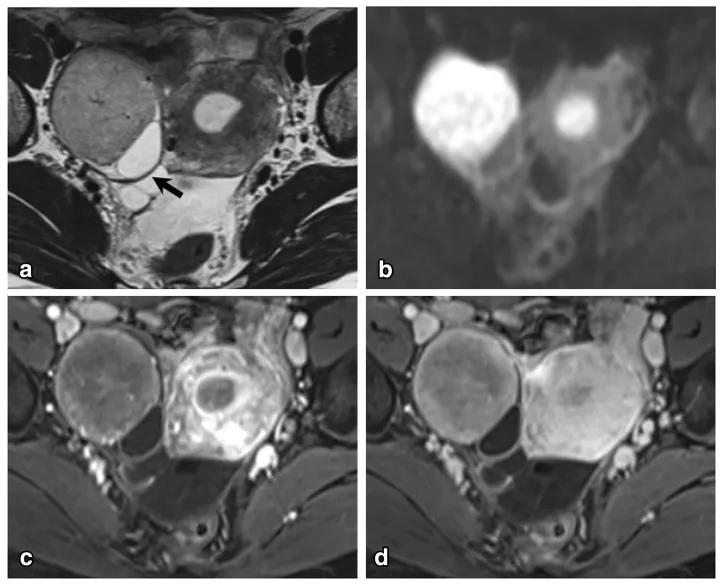

女,65 岁,左侧卵巢纤维瘤。图 a 箭头显示肿物 T2WI 呈低信号,DWI 未见明显扩散受限(b),增强扫描缓慢强化(c 增强早期,d 增强晚期)